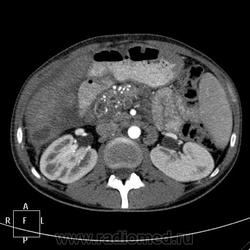

КТ (часть кадров выложу позже ). Цель направления на КТ - образование правой доли печени, исключить образование тела п.ж.

). Цель направления на КТ - образование правой доли печени, исключить образование тела п.ж.

Панкреатическая:

Портальная:

В данном случае ранняя артериальная получилась с брачком - контрастировалась нижняя полая (25 сек задержка, триггера нет), панкреатическая 45 сек (стандарт), портальная 70 сек. Отсроченная в печени делается на подозрение на холангиокарциному и гемангиому. Тут почки и не интересовали.

Гемангиома, являясь сосудистой опухолью, будет такого же цвета, как и сосуды, во все фазы. Это - кистовидное образование, стенки относительно равномерной толщины, копящие контраст тонкой полоской. Содержимое образования жидкостной плотности и контраст не копит.

Гепатоспленогмегалия. Начальная портальная гипертензия, холедох не расширен. В воротах печени бугристая масса.... чего? Кальцинаты поджелудочной железы, мелкий камушек в желчном. Вопрос в том, что за кистовидное образование, что за полоса-серп вокруг желчного пузыря, что в воротах печени. Опухоли п.ж. я не нашла.

Данному пациенту в заключении я выставила подпеченочный абсцесс, гепатоспленомегалию, портальную гипертензию, конгломерат лимфоузлов ворот печени, лимфаденопатию желудочной группы л/у, хр.калькулезный панкреатит, ЖКБ с перихолециститом.

В воротах, похоже л/у, а жидкостное абсцесс печени.

Абсцесс печени.